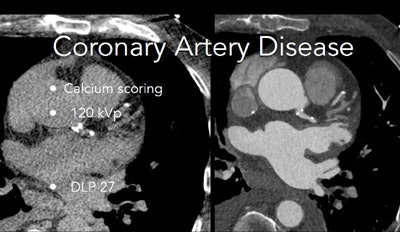

For ruling out coronary artery disease, the new system allows for single-beat acquisition of the heart, regular breathing during the scan, low kVp, and high-pitch spiral acquisition that enable scanning with usually less than 40 mL iodinated contrast and usually less than 1 mSv of radiation dose, noted Becker, a professor of radiology at Ludwig-Maximilians University, Grosshadern Clinic in Munich.

Calcium scoring exam was acquired at 120 kVp.The relationship between heart rates and image clarity remains somewhat variable. Scan quality is better at lower heart rates. But using the scanner daily in a busy clinic, the group has found the high-pitch scan mode capable of delivering very clear images in fast hearts. Even so, "some patients with lower heart rates ... tend to have motion [artifacts] in scans acquired with high-pitch mode," he said.